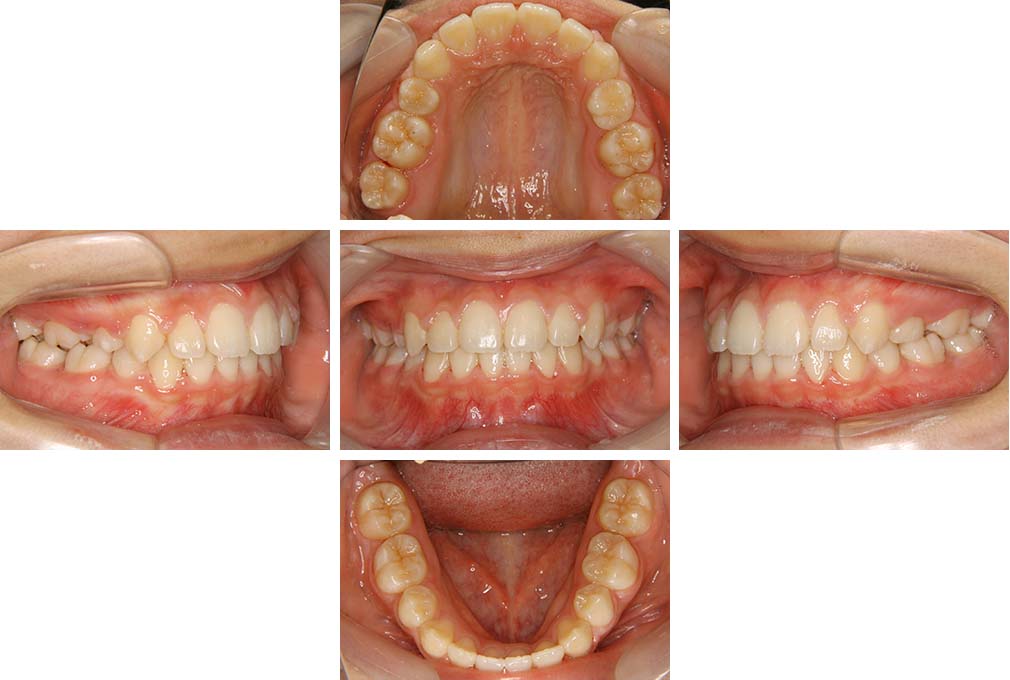

CASE:04

アングルⅢ級傾向を持つ叢生

初診時年齢 22歳

性別 女性

治療費の目安 105万円程度(治療開始時)

上顎右側犬歯が唇側に転位していることを主訴に県内歯科医院から紹介来院された。骨格的にはⅢ級傾向で上顎右側犬歯が唇側転位となり、側切歯が口蓋側に転位していた。下顎前歯が叢生になっていることも相まって上下の正中線は右側に大きくずれていた。アングルⅢ級傾向を持つ上下顎前歯部叢生と診断した。

上下顎小臼歯を抜歯していただき上顎舌側、下顎唇側マルチブラケット装置を使用して動的治療を行った。矯正用ゴムの使用など協力状態も良く、正中線の大きな移動があったのも関わらず2年10カ月で装置を撤去し保定へ移行した。保定移行後14年が経過し、ご息女の診察でご来院いただいていたことから、口腔内を拝見したが、下顎前歯のわずかなずれがあったものの大きな歯列の乱れはなく歯列は安定していた。動的治療期間2年10カ月間。

治療前

22歳6か月

治療後

動的治療期間2年10カ月間

25歳6か月

治療終了

動的治療終了後2年2カ月

28歳8か月

14年経過

動的治療終了後14年7カ月

40歳1か月